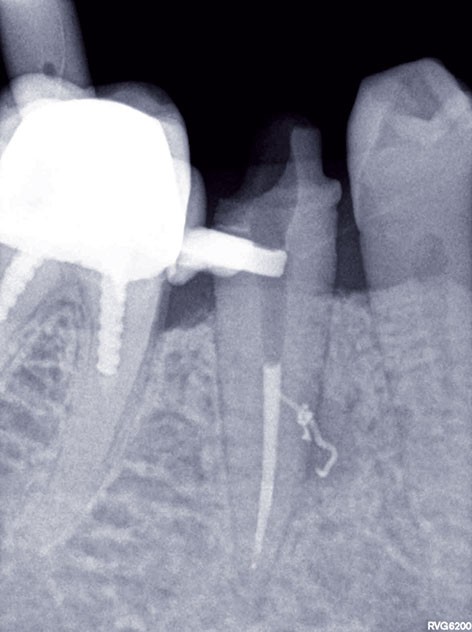

3, 4, 5. La restauration est déposée, les tissus carieux éliminés et la cavité d’accès aménagée avant la réalisation du traitement endodontique. La radiographie postopératoire permet de visualiser l’obturation du canal latéral en regard de la LIPOE.